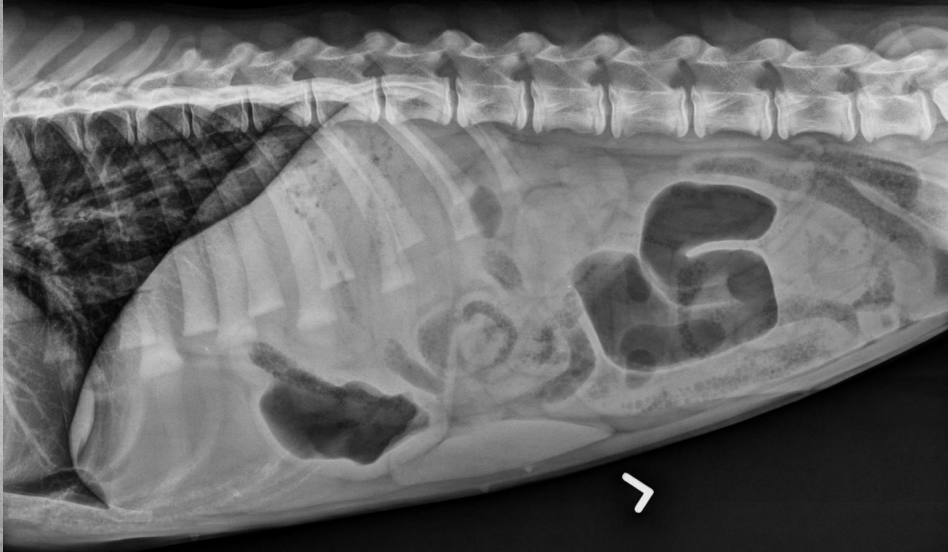

15 yo cat

Weight loss, anorexia, vomiting

Findings:

● Dilated bowel filled with fecal mass

– Not only large intestine, but small

intestine as well.

● Megacolon